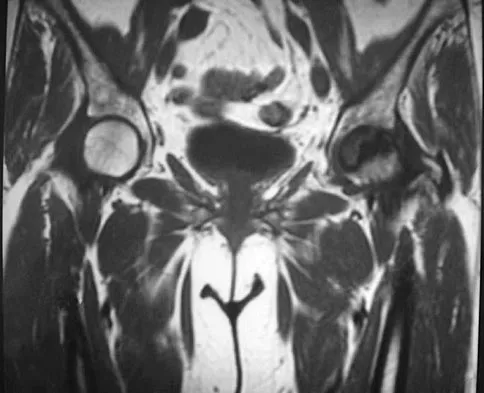

A 5-year-old girl has had a low-grade fever, right hip and buttock pain, and a right-sided limp for the past 5 days. Examination shows diffuse tenderness and extreme pain on range of motion of the hip. Laboratory studies show a peripheral WBC count of 13,500/mm3 and an erythrocyte sedimentation rate of 55 mm/h. A radiograph is shown in Figure 46a, and an axial postgadolinium T1-weighted MRI scan with fat suppression and an axial T2-weighted fast spin echo MRI scan are shown in Figures 46b and 46c. What is the most likely diagnosis?

Explanation